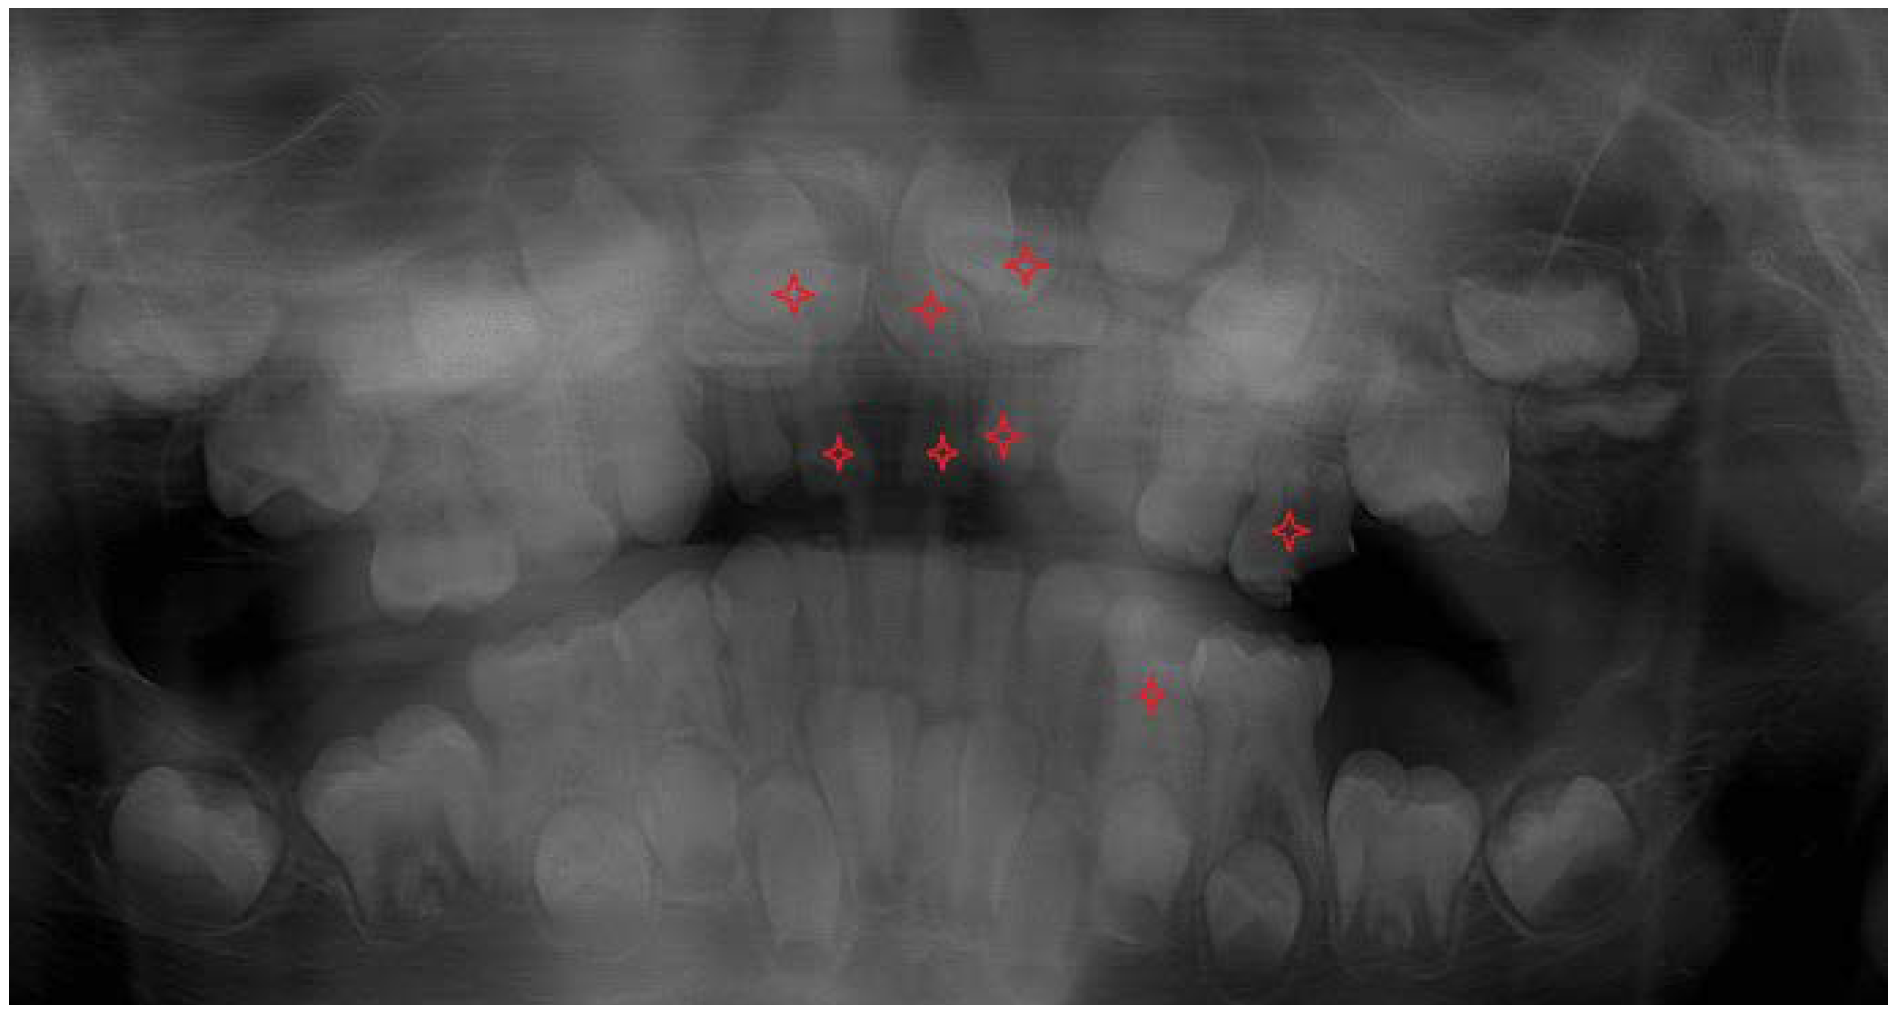

On the panoramic radiographic image (OPG) taken in April 2013 (Figure 1.) there was a finding of over-retained deciduous teeth with unresorped roots. The dental age was estimated according to the Demirjan method, 4,6 years in the upper dental arch and 6,9 in the lower. Three supernumerary teeth were present in the upper jaw, and two in the lower, displacing the developing permanent teeth and obstructing their eruption. All regular permanent teeth buds were in place, some of them were retarded in eruption also because of a lessened eruptive potential. There was a serious (approximately 3 years) delay in the root development of the permanent teeth. The dental age was estimated according to the developmental stages of the roots of permanent teeth and resorption stages of deciduous predecessors – the Demirjan method [19,22].

The three-dimensional (3D) reconstruction of the CBCT x-ray, taken in May 2013 revealed three more supernumerary empty tooth crypts in the upper jaw and proved the two supernumerary teeth in the lower. The patient had had 8 supernumerary teeth at that time. (Figure 1.,6.,7.)

Two surgical interventions in general anesthesia were planned in the upper jaw, provided that no more supernumerary teeth develop from empty, non-mineralized supernumerary dental crypts, which are usually difficult to localize on early CBCT scans. One surgical intervention under general anesthesia was planned in the lower arch to extract the two supernumerary teeth in the premolar area. (Figure 1)

Figure 1. The initial OPG x-ray of the patient (2013).